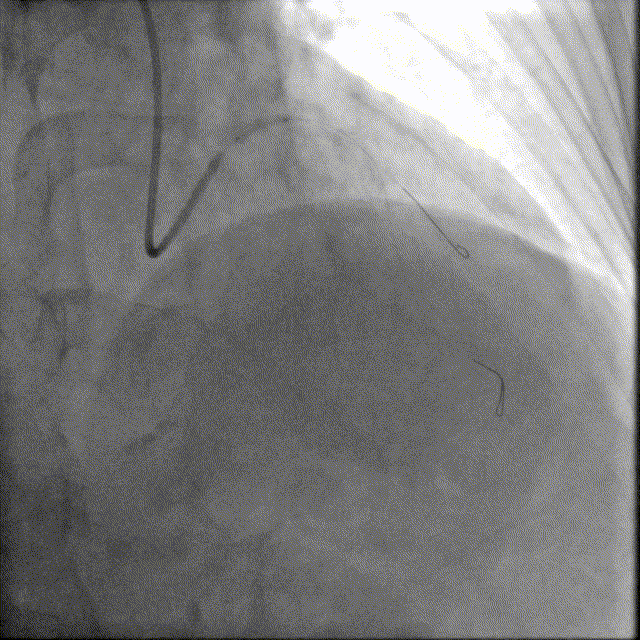

选择EBU指引导管,以2.0预扩张球囊及2.5×12mm耐高压球囊预扩前降支近段病变,可见不同程度的球囊膨胀欠佳。

冲击波导管送至左前降支,由中段至开口依次以4atm压力初始冲击扩张,6atm压力巩固扩张,共冲击扩张10秒×8个周期,可见球囊逐渐膨胀充分。此阶段在处理前降支开口时预置回旋支保护导丝。

预处理效果满意。